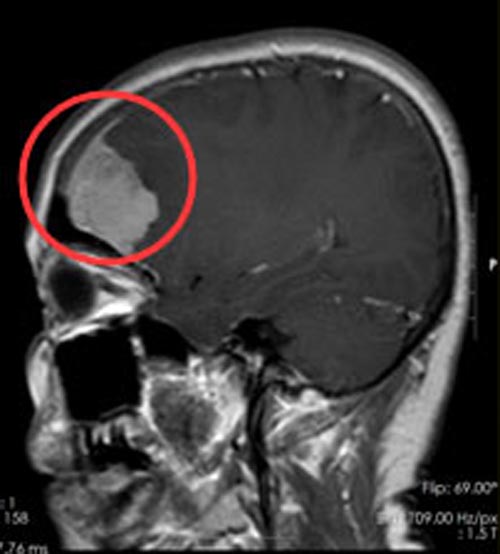

两个月前黄阿姨不慎摔伤了左手臂,在当地医院检查的时候,顺便做了头颅CT检查,还真有了意外发现:左侧额叶占位,进一步的头颅磁共振检查提示:右额额叶病变,考虑脑肿瘤。

家人都觉得手臂的事小,脑肿瘤的事不小,赶紧陪着她来到了广东三九脑科医院入住综合神经外科。由于肿瘤占位效应明显,医生建议手术治疗,排除手术禁忌症后,在全麻下为黄阿姨行“经右额行右侧额部肿瘤切除术”,术中可见肿瘤血供丰富,显微镜下整块全切肿瘤,术程顺利。术后第三天,黄阿姨言语对答切题,视力视野未见异常,除摔伤的左上肢肌力III级外,余肢体肌力肌张力正常。术后病理:脑膜皮细胞型脑膜瘤。